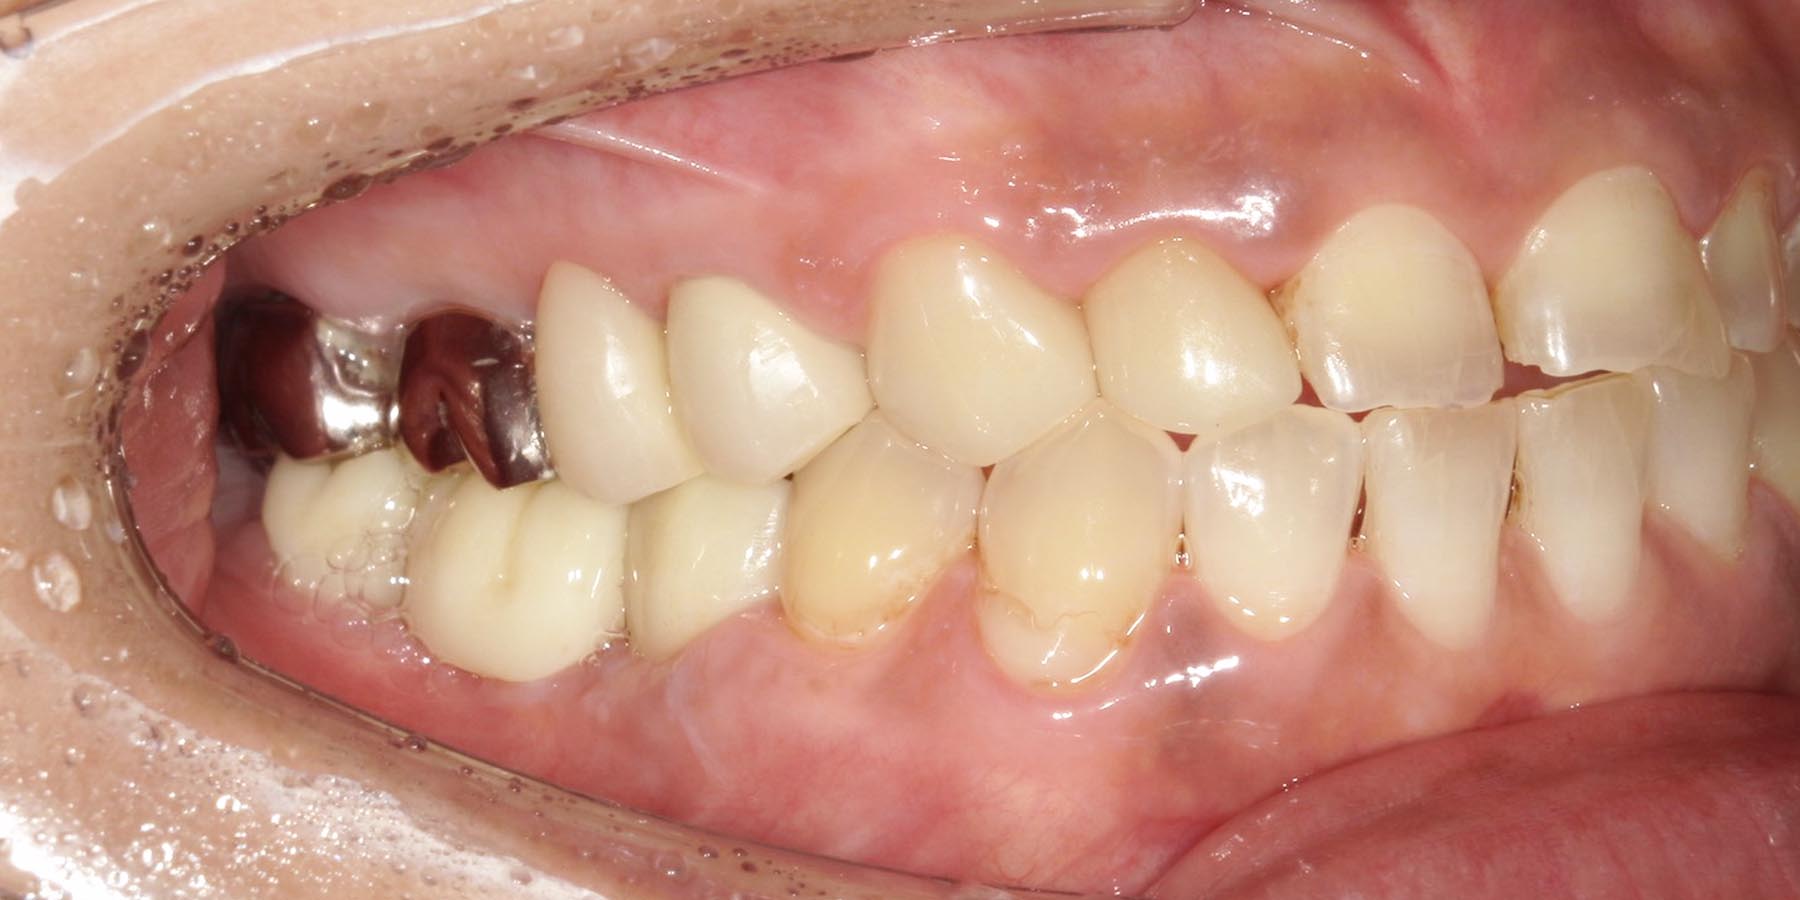

治療前